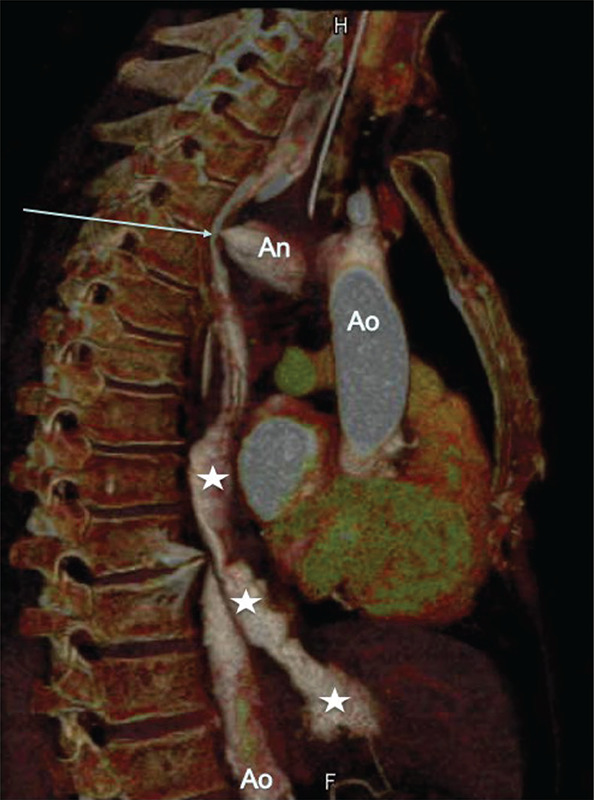

Aorto‑esophageal fistulas (AEF) are rare, often fatal connections between the thoracic aorta and esophagus, arising from aortic disease, esophageal conditions, or iatrogenic causes. Case: A 76‑year‑old woman, treated for esophageal nutcracker syndrome with endoscopic injection of botox, developed chest pain and esophageal hemorrhage. Computed tomography (CT) confirmed an AEF from an aortic pseudoaneurysm. She succumbed to circulatory collapse before treatment. Discussion: Endoscopic botox injections are a rare cause of AEF. The diagnosis relies on imaging and endoscopy, with surgery often required. Teaching point: Aorto‑esophageal fistulas are rare, life‑threatening complications, particularly after iatrogenic procedures. Early diagnosis is crucial, but prognosis remains poor.